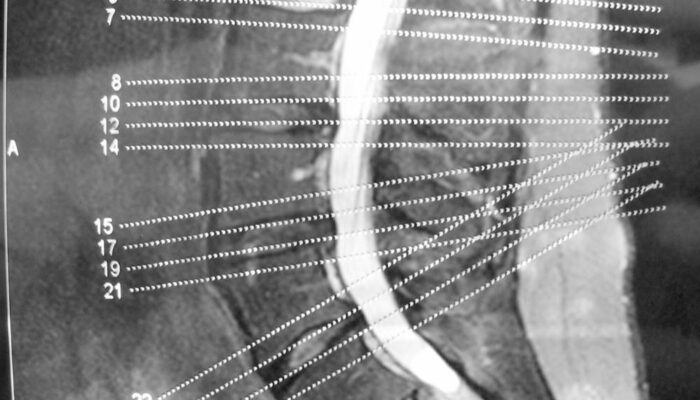

A brief overview of degenerative disc and joint disease

When you mention the term degenerative disease, it refers to the gradual deterioration of the body tissues or cells over the years due to the natural aging process. As we age, our spine starts giving in to the stress of providing flexibility and support to our back. The components of the spine start deteriorating slowly, and you will experience back pain and stiffness in the spine.